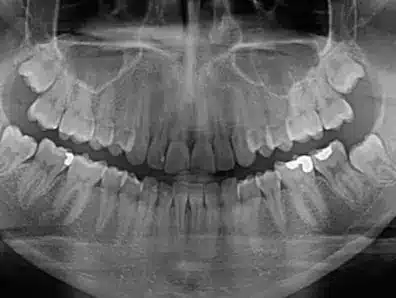

Una radiografía dental panorámica permite a tu dentista ver con todo detalle el estado de tu boca, dientes, hueso.

La odontopantomografía se conoce también como rayos X panorámicos, es un examen dental en 2D que permite capturar una imagen completa de la boca.

La radiografía ortopantomografía permite detectar problemas dentales mediante una imagen completa de los maxilares, la mandíbula y los dientes.

Permite observar con gran nitidez los dientes, la mandíbula y sus articulaciones, el área nasal y los senos maxilares.